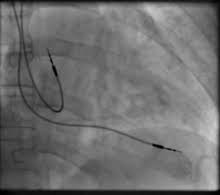

This type carries electrical impulses to the right ventricle and the right atrium of your heart to help control the timing of contractions between the two chambers. Learn what pacemakers are and what they do, how they are implanted, and what to expect if you have or need one. Pacemaker ships with most modern linux distributions and has been deployed in many critical environments including deutsche flugsicherung. It consists of a pulse generator, which has a battery and a tiny computer circuit, and 1 or more wires known as pacing leads, which attach to your heart. A pacemaker is a small device that's placed under the skin of the chest or abdomen to help control abnormal heart rhythms. How often should it pace? An overview of pacemakers, including the history of pacemakers, the different types of pacemakers and how each of these work in practice. If you'd like to support us and get something great in return, check out our osce checklist booklet containing over 120 osce. Pacemakers are devices that detect the electrical activity of the heart and stimulate it to contract at a faster rate. How do pacemakers regulate arrhythmias? Most pacemakers have a sensing mode that inhibits the pacemaker from sending impulses. Many, many developers have contributed significantly to the project. The pacemaker's pulse generator sends electrical impulses to the heart to help it pump properly.

Pacemaker is distributed by clusterlabs. Pacemakers provide electrical stimuli to cause cardiac contraction during periods when intrinsic cardiac electrical activity is inappropriately slow or absent. The wires with electrodes are inserted into the right. An electrode is placed next to the heart wall and small electrical charges travel through the wire to the heart. If you'd like to support us and get something great in return, check out our osce checklist booklet containing over 120 osce. Most pacemakers have a sensing mode that inhibits the pacemaker from sending impulses. One design, the subcutaneous icd. It consists of a pulse generator, which has a battery and a tiny computer circuit, and 1 or more wires known as pacing leads, which attach to your heart. It implements several apis for controlling resources. Learn what pacemakers are and what they do, how they are implanted, and what to expect if you have or need one. Pacemakers provide electrical stimuli to cause cardiac contraction, pacing systems consist of a pulse generator and pacing leads. Searching meanings in arabic can be beneficial for understanding the context in an efficient manner. Learn about pacemakers, including the difference between transvenous and leadless (wireless) pacemakers, why you may need one, how they're placed, and information about living with the device.

Figure a shows the location and general size of a double chamber, or double lead, pacemaker in the upper chest. An electrode is placed next to the heart wall and small electrical charges travel through the wire to the heart. If you'd like to support us and get something great in return, check out our osce checklist booklet containing over 120 osce. How often should it pace? How do pacemakers regulate arrhythmias?